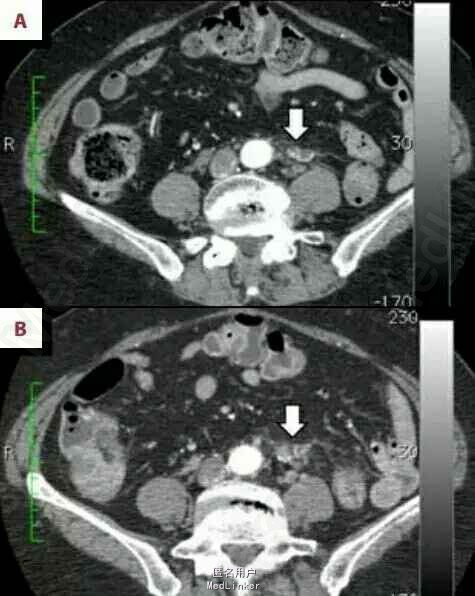

1年半后患者CT检查提示腹主动脉分叉处左侧见一边界模糊,非肿瘤性病灶,血供丰富。考虑为术后结缔组织的炎症反应。随后几次复查发现该病灶形态逐渐改变。术后3年CT检查结果显示病灶体积增大,但放射学检查依旧认为是良心病变。术后5年复查,上述病灶在CT上呈实性肿瘤样改变,其内可见骨针形成,怀疑为结肠癌术后局限性复发。但CEA和CA199等肿瘤标记物未见异常。为证实肿瘤存在,患者行FDG-PET/CT检查。检查结果示:上述病灶呈明显FDG高摄取,除上述病灶外未发现其他存在病灶,诊断为局限性结肠癌复发。